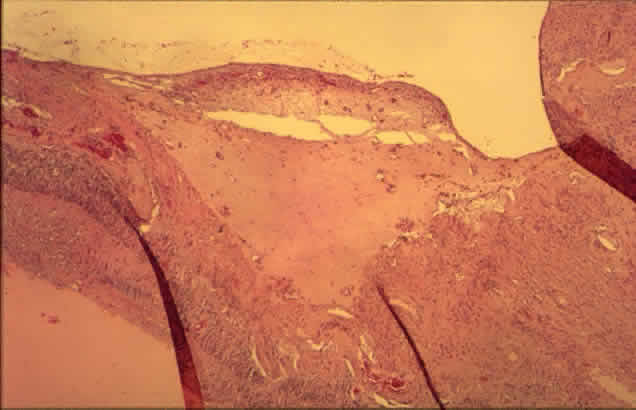

Histologically, new vessels develop between the retinal surface and the posterior surface of the formed vitreous (Fig. 12). With NVE, there is a demonstrable break through the internal limiting membrane (Fig. 13).20 Early-developing new vessels have lumina even at the proliferating tips.53 Active new vessels have endothelial cells and pericytes, with fenestrations. Morphologically, fenestrations are areas ranging from 40 to 80 nm in diameter where the cell membranes are focally fused, and are normal findings in capillaries outside of the retina and brain. They allow increased permeability and are responsible for the diffuse leakage of fluorescein seen from new vessels on angiography. Inactive or “ghost” new vessels are acellular, having lost both endothelium and pericytes.39 With time, fibrous tissue develops and accompanies the new vessels. The vessels themselves may leak and bleed into the vitreous, leading to visual loss.

Fig. 12. Neovascularization at the disc with fibrous proliferation. The fibrovascular membrane overlies the internal limiting membrane, which is wrinkled (arrows). The retinal detachment is artifactual. (PAS, × 19.5)

Fig. 13. Neovascularization away from the disc. The fibrous tissue has contracted, imparting a triangular shape to the membrane. Active new vessels are present throughout. The dark folds are artifactual. (H&E, × 31.25)

The fibrous tissue is contractile, and has been shown to contain actin filaments.54 Clinically, fibrous proliferation appears as whitish bands on the retinal surface, sometimes obscuring the neovascularization. With retinal elevation, retroretinal membranes also can form.

Traction can cause cystoid changes in the retina20 and venous loops,55 as well as retinal detachment (Color Fig. G). Extensive traction can cause macular heterotopia reminiscent of retinopathy of prematurity.56